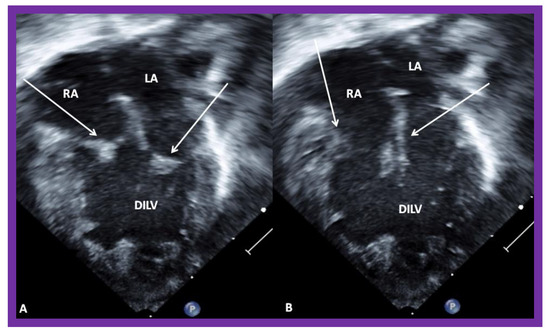

Figure 4.

Echocardiograms in apical four-chamber views of a baby with double inlet left ventricle (DILV) with closed (A) and open (B) atrioventricular valves (arrows). The outlet chamber is not visualized in this view. LA, left atrium; RA, right atrium. Reproduced from Reference [15].